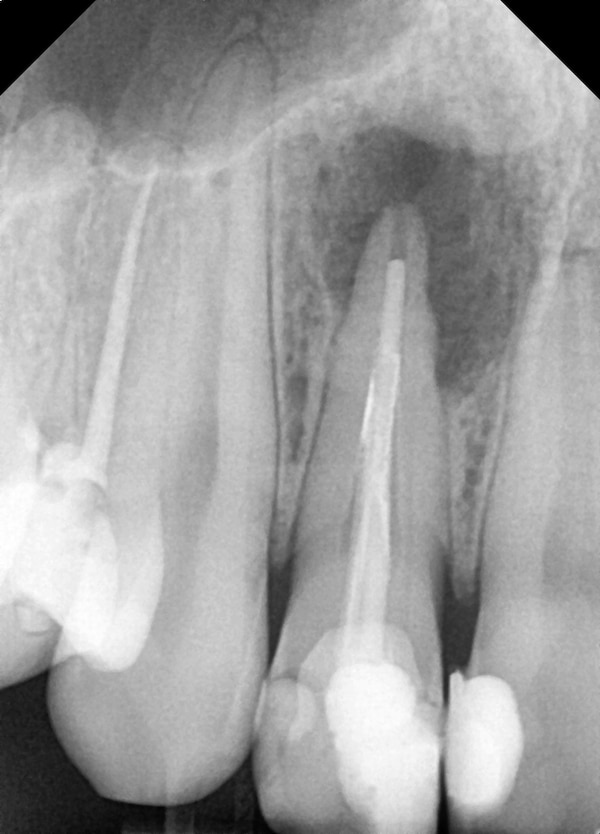

Marković Dental Clinic uglavnom radi jednoposjetnu strojnu endodonciju uz „apex lokator“uređaj kojim mjerimo točnu dužinu korijenskog kanala, takav pristup omogućuje najbolje rezultate i skraćuje vrijeme trajanja zahvata, dezinfekciju po najmodernijim protokolima, te punjenje biokompatibilnim materijalima uz obaveznu kontrolu punjenja rendgentskom slikom (RVG 2D).